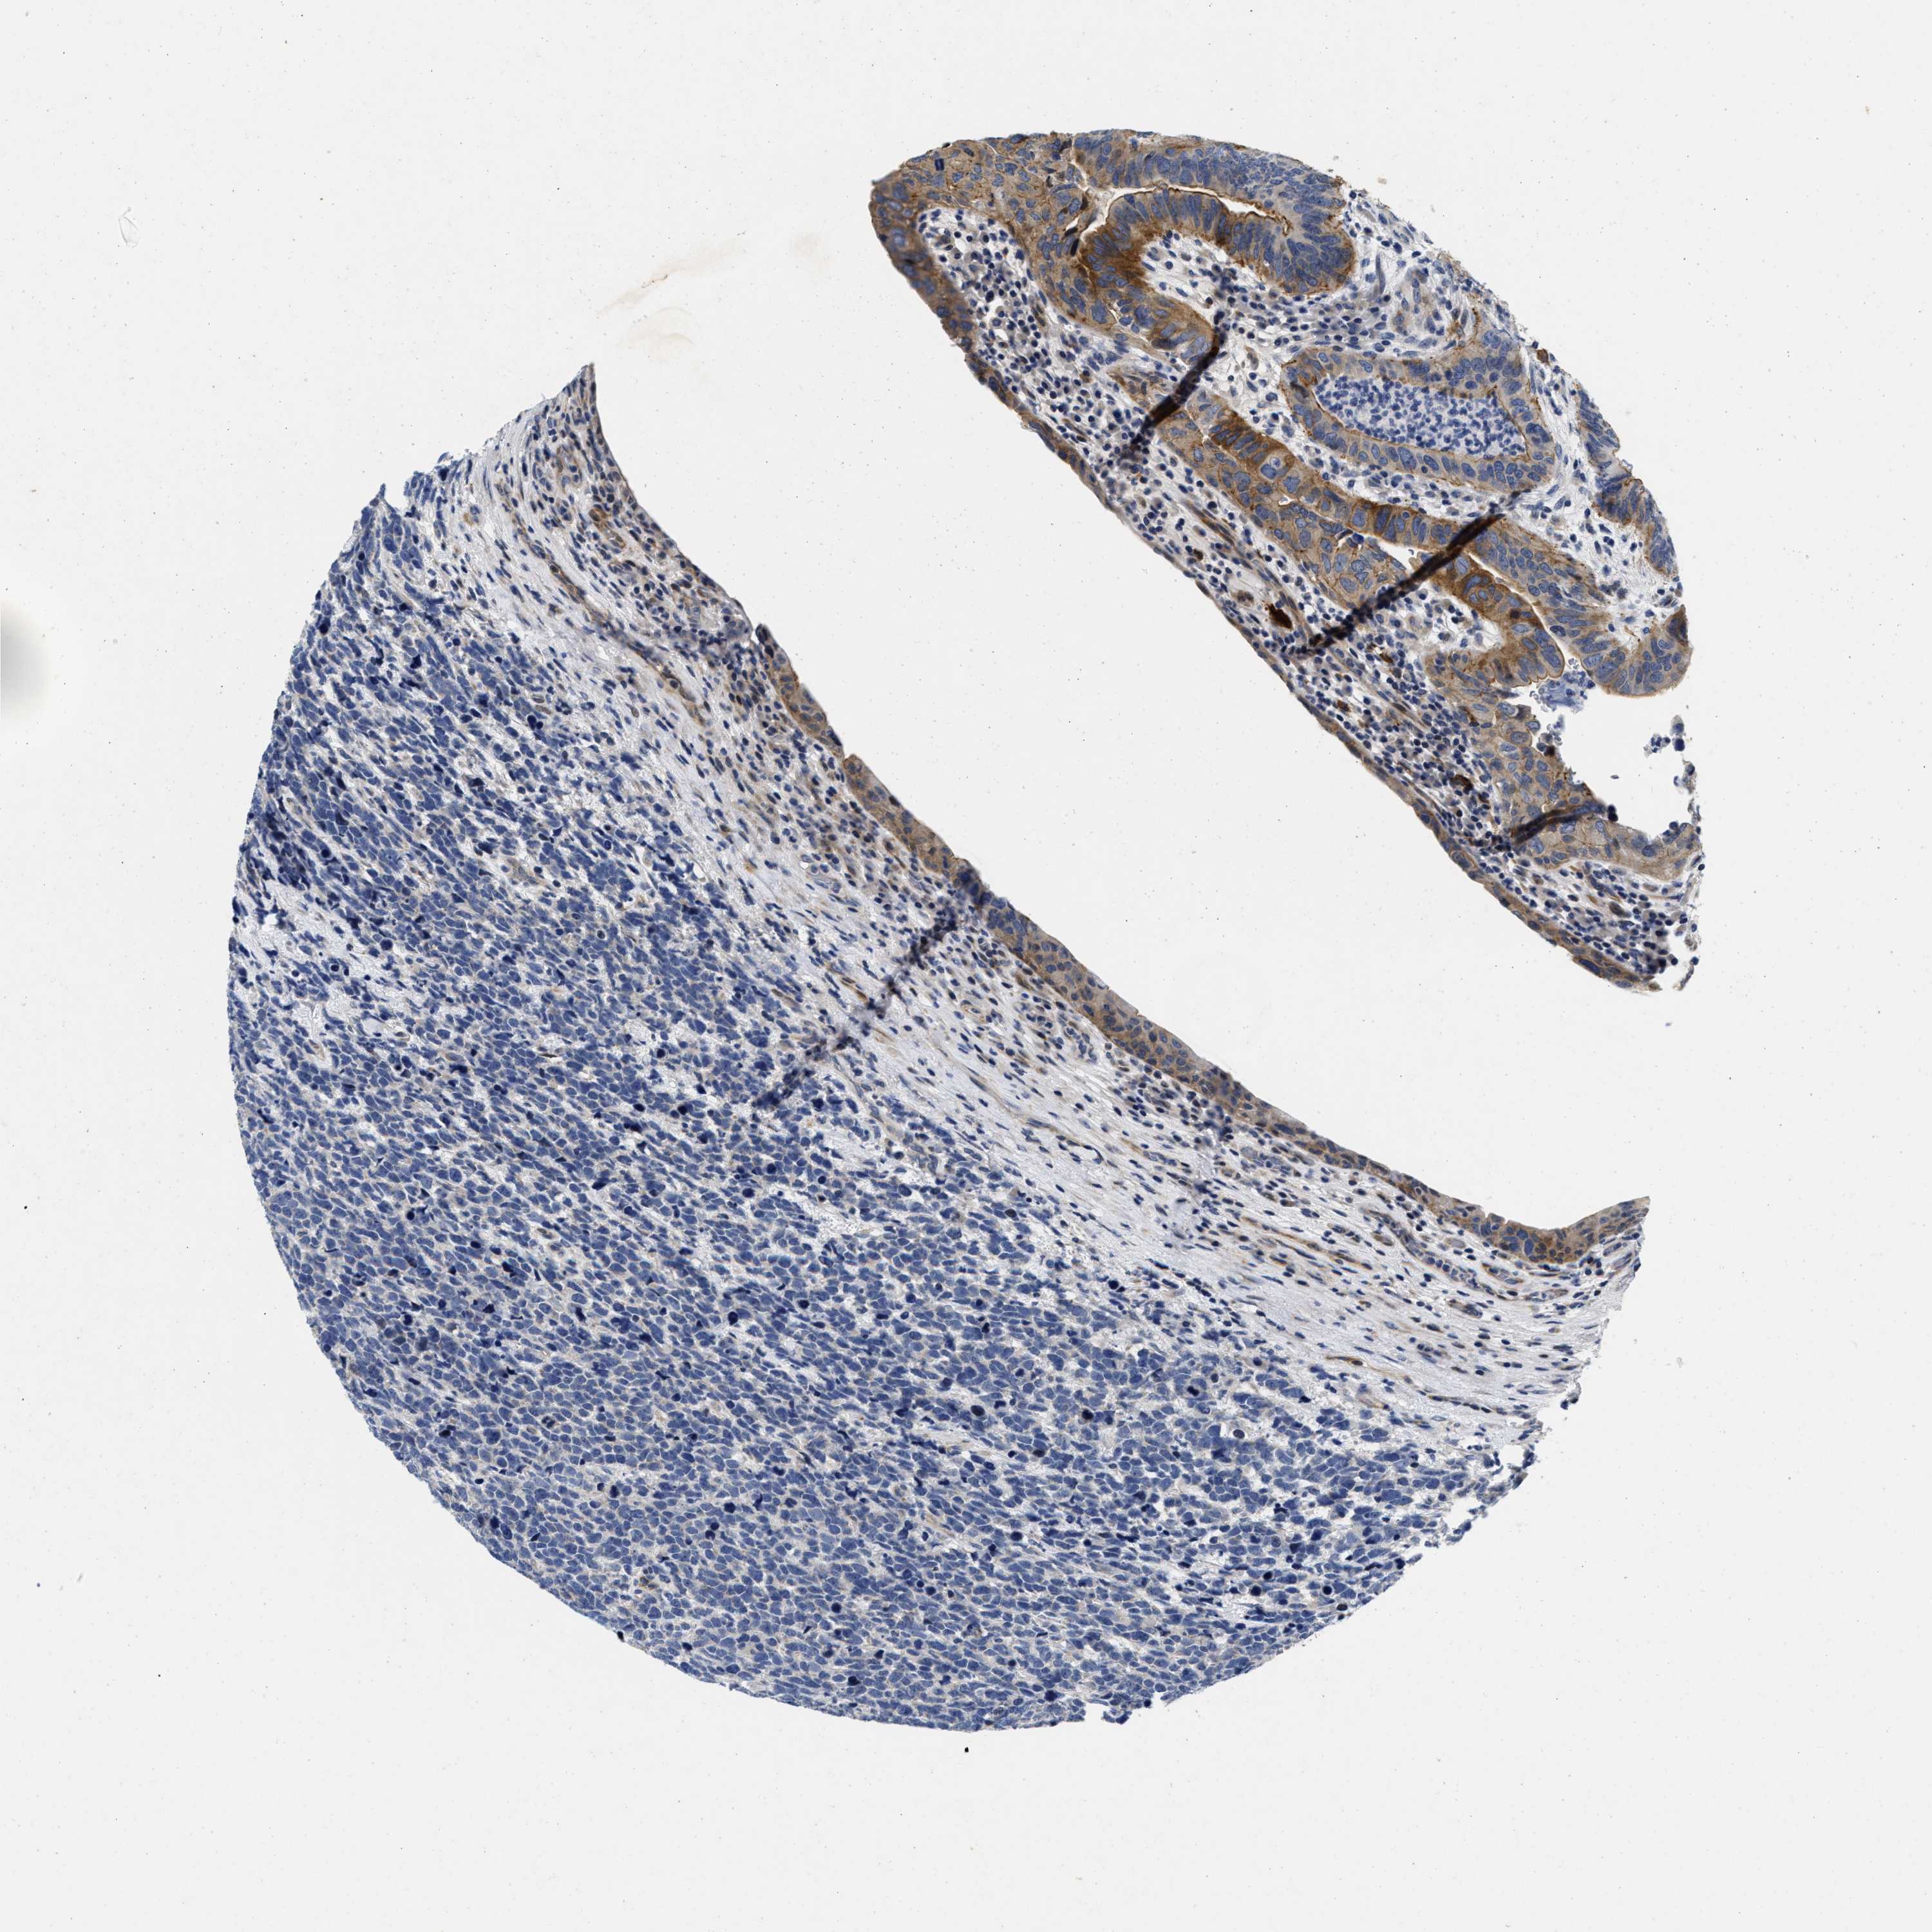

UROTHELIAL CANCER - Protein expressioni

A mouse-over function shows sample information and annotation data. Click on an image to view it in a full screen mode. Samples can be filtered based on level of antibody staining by selecting one or several of the following categories: high, medium, low and not detected. The assay and annotation is described here.

Note that samples used for immunohistochemistry by the Human Protein Atlas do not correspond to samples in the TCGA dataset.

Antibody stainingi

Antibody staining in the annotated cell types in the current human tissue is reported as not detected, low, medium, or high, based on conventional immunohistochemistry profiling in selected tissues. This score is based on the combination of the staining intensity and fraction of stained cells.

Each image is clickable and will lead to virtual microscopy that enables deeper exploration of all samples and also displays staining intensity scores, fraction scores and subcellular localization as well as patient and tissue information for each sample.

Antibody HPA007256

Antibody HPA028732

Staining

High

Medium

Low

Not detected

Intensity

Strong

Moderate

Weak

Negative

Quantity

>75%

75%-25%

<25%

None

Location

Nuclear

Cytoplasmic/membranous

Cytoplasmic/membranous,nuclear

Urothelial carcinoma, Low grade

Urothelial carcinoma, High grade